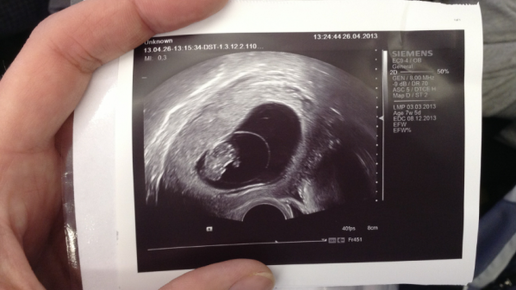

Развитие эмбриона Многие тысячи, молодых девушек, лишь только тест покажет заветные две полоски, спешат набрать в поисковике глобальной сети запрос: «первая неделя беременности – развитие эмбриона». Им не терпится почитать, как поживает под сердцем будущий ребенок. Это материнский инстинкт переданый от Матушки Природы. Однако, как мы и говорили в предыдущем разделе, 1 неделя беременности по акушерскому методу отсчета (не путайте с 1 эмбриональной неделей беременности, которая наступит на 14 дней...